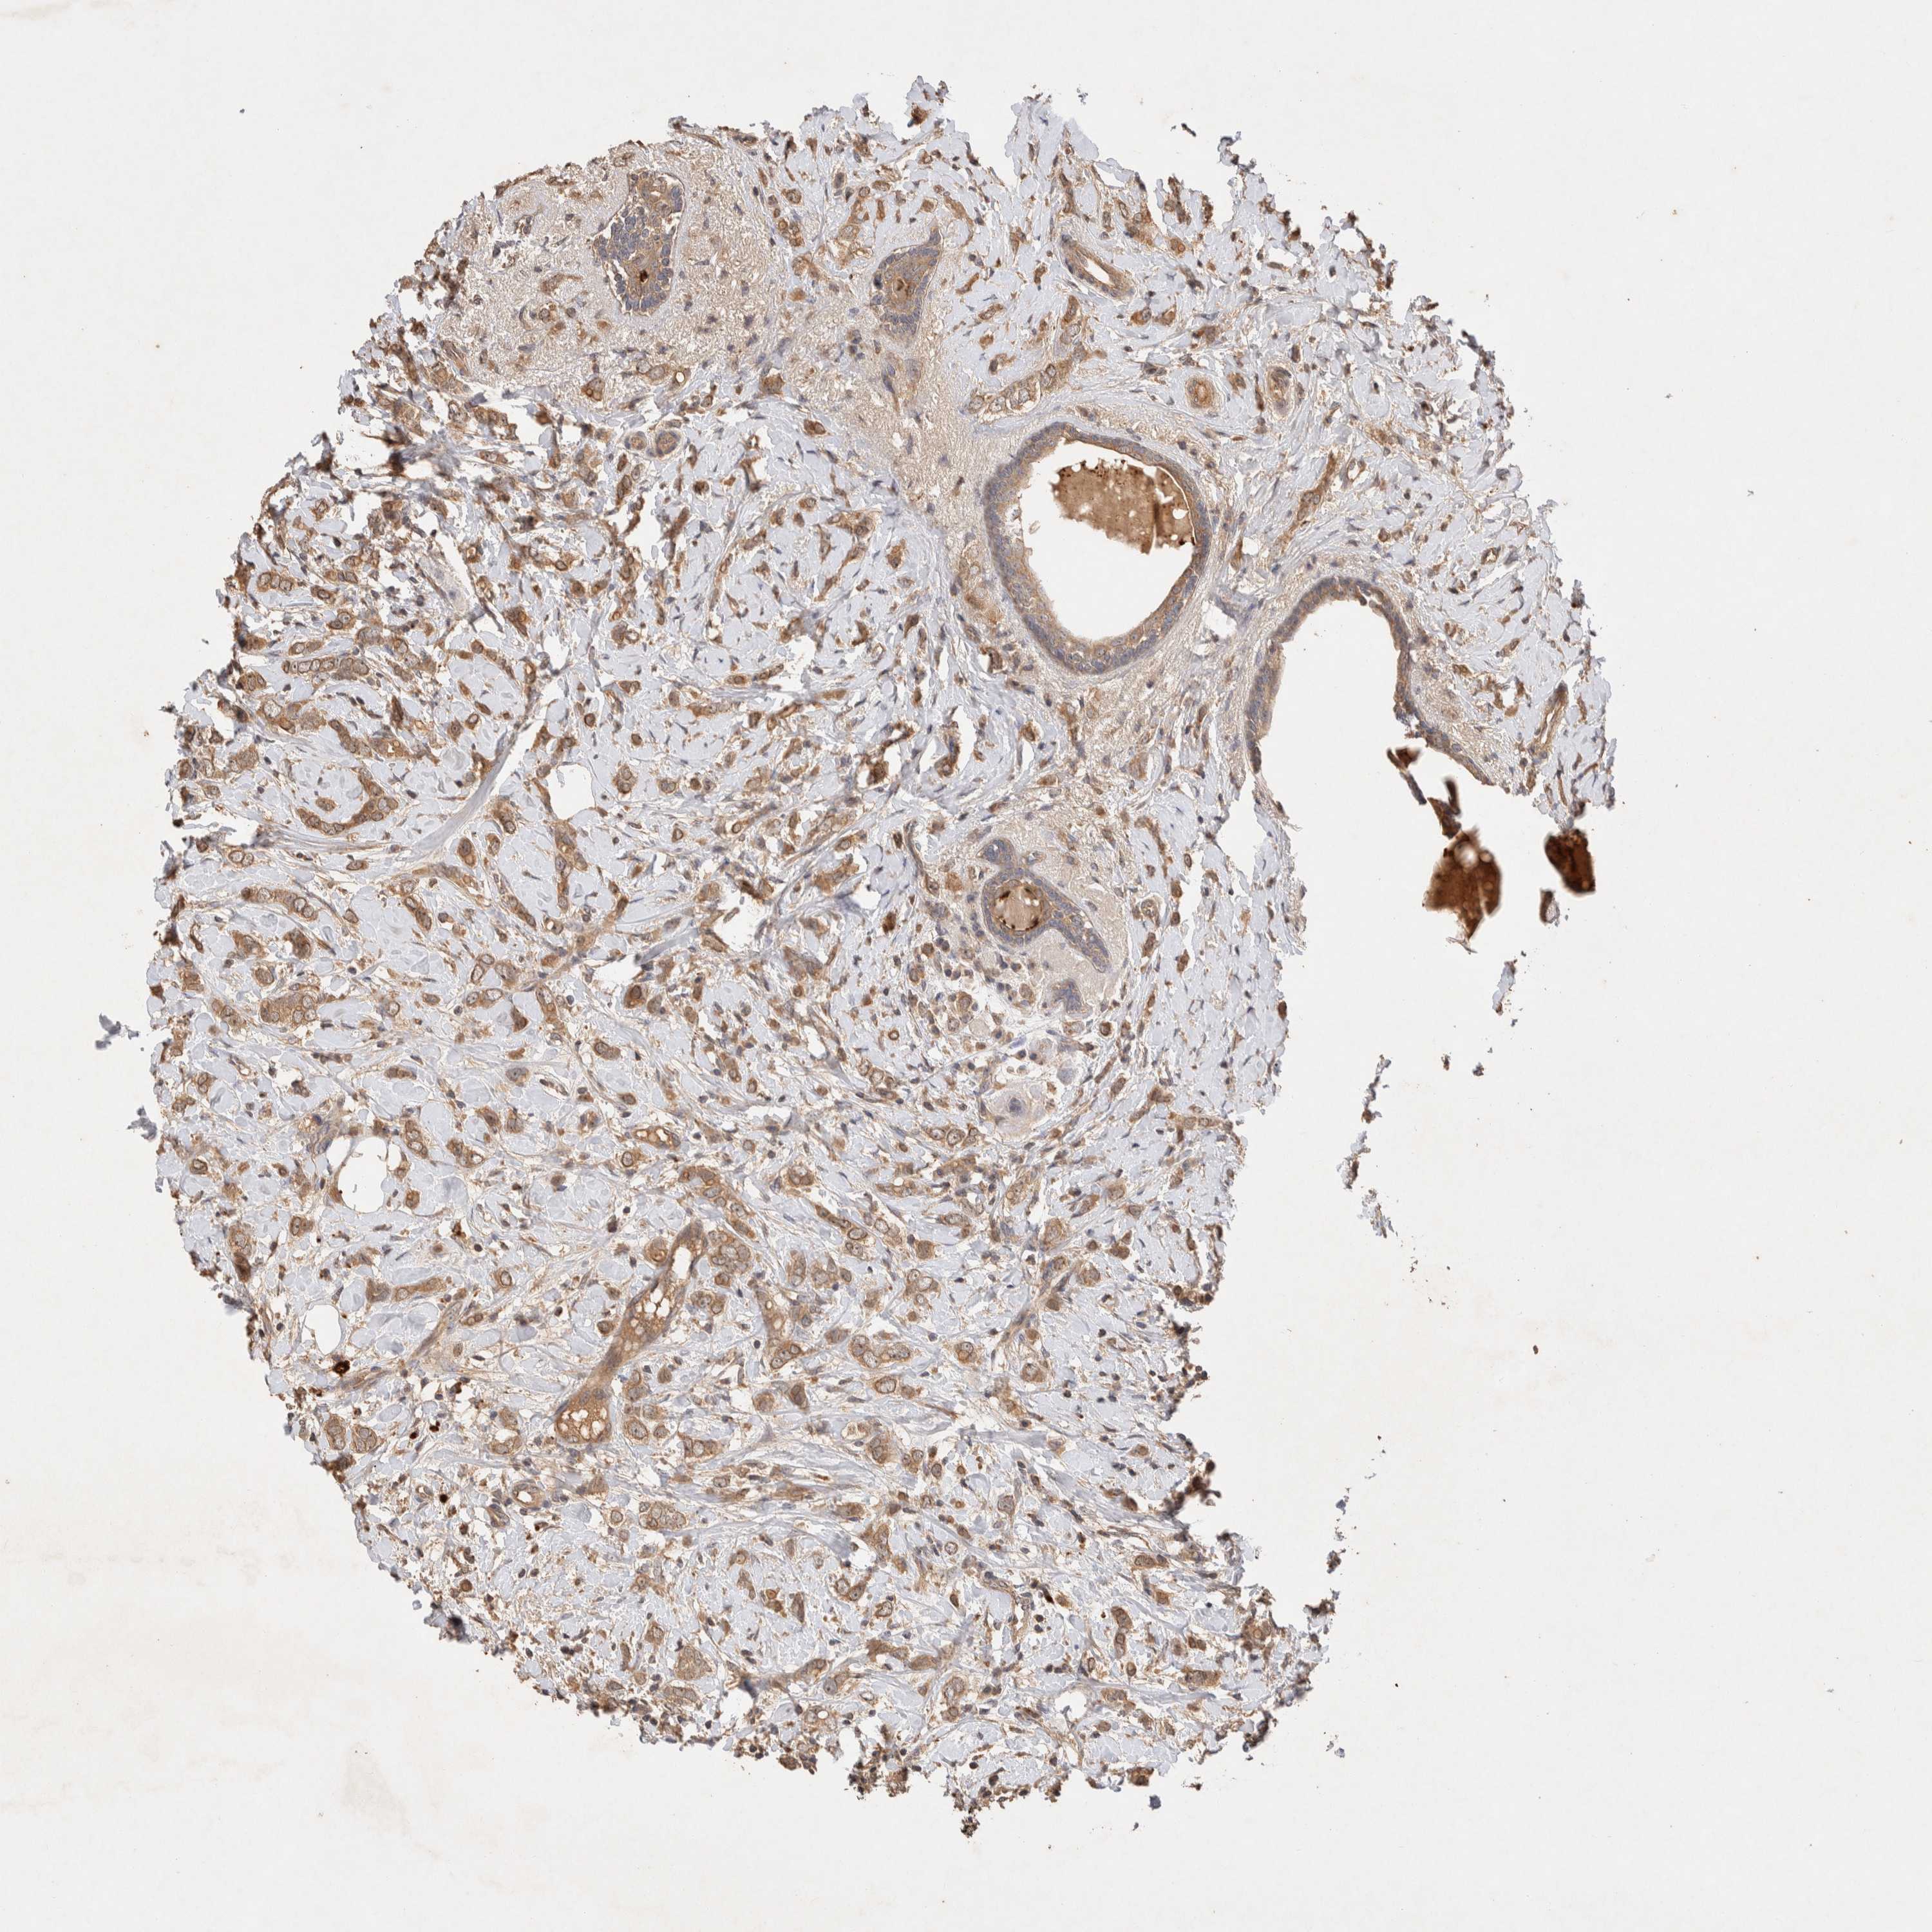

CANCER BREAST CANCER Show tissue menu

BRCA TCGA BRCA VALIDATION PROTEIN EXPRESSION